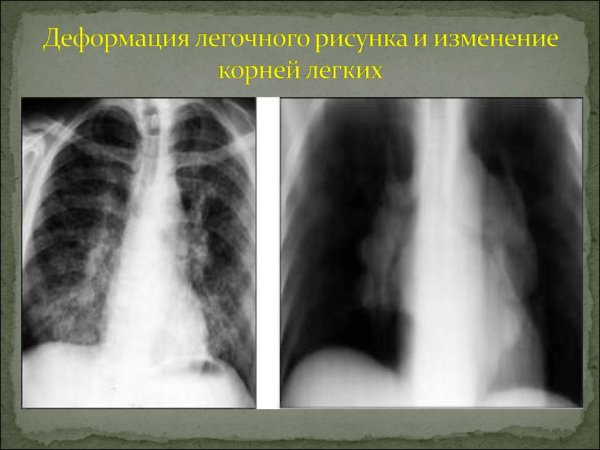

Деформация легочного рисунка - это состояние, при котором образование и распределение сосудистых и бронхиальных структур в легких претерпевает изменения. Это может быть следствием различных заболеваний, например, хронической обструктивной болезни легких (ХОБЛ), бронхоэктазов, фиброза легких или эмфиземы. Как результат, легочный рисунок становится нарушенным, что приводит к ограничению функции дыхания и возможному ухудшению общего состояния пациента. Для диагностики и оценки деформации легочного рисунка используются различные методы, такие как рентгенография грудной клетки, компьютерная томография или магнитно-резонансная томография. Лечение деформации легочного рисунка зависит от основного заболевания и может включать фармакотерапию, физиотерапию или хирургическое вмешательство.